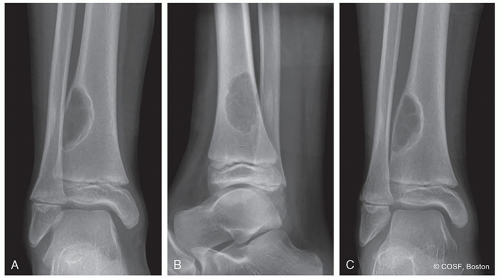

How is the bone responding to the tumor: margination, periosteal reaction? (Figures 41.1,41.2,41.3,41.4,41.5,41.6,41.7,41.8,41.9)

Epiphysis: chondroblastoma in skeletally mature, giant cell tumor in adult (see Figures 41.2 and 41.8)

Metaphysis: Benign—nonossifying fibroma, osteochondroma, unicameral bone cyst, aneurysmal bone cyst, chondromyxoid fibroma (see Figure 41.1)

Malignant: osteosarcoma chondrosarcoma, undifferentiated pleomorphic sarcoma of bone (see Figure 41.3)